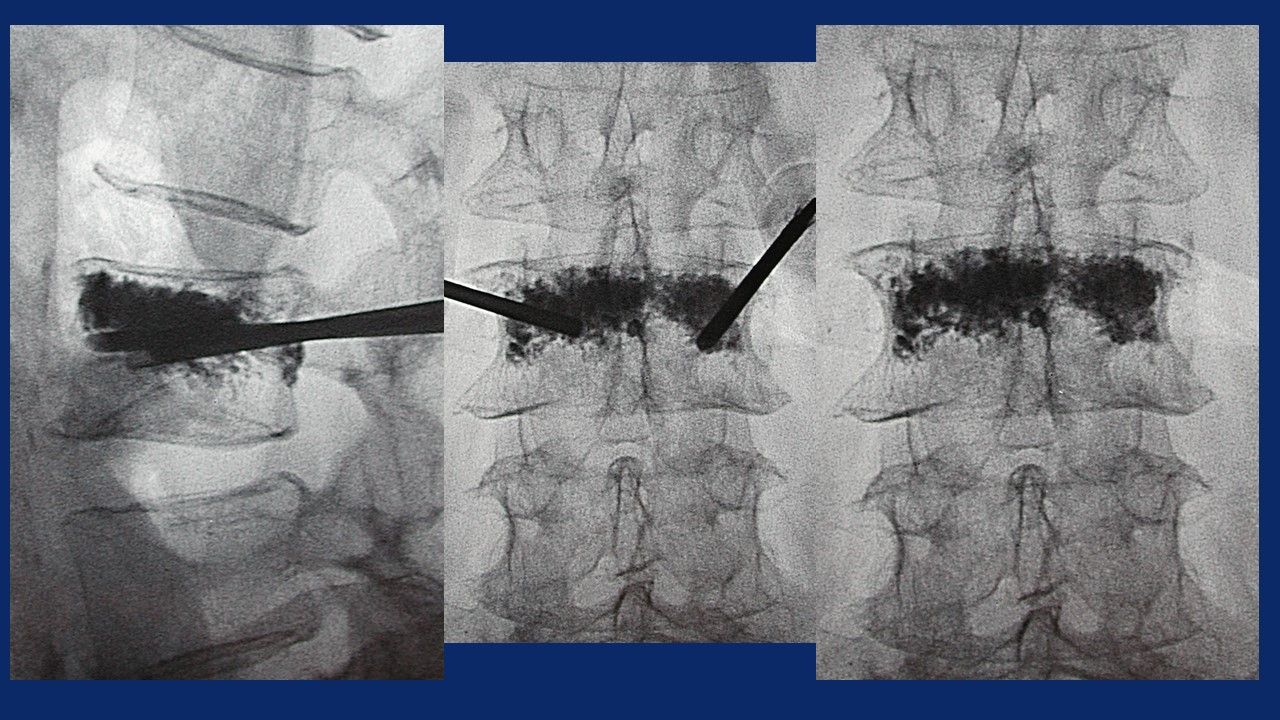

- nel trattamento delle fratture vertebrali, su base osteoporotica o neoplastica mediante Vertebroplastica, Chifoplastica, Osteoplastica, Termoablazione o Crioablazione con Osteoplastica

Vertebroplastica

Cifoplastica

Crio e Termoablazione con osteoplastica